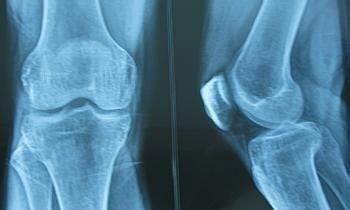

X线平片在早期并无明显异常,约数年后才逐渐出现关节间隙狭窄,此表明关节软骨已开始变薄。起初,关节间隙在不负重时正常,承重后出现狭窄。病变后期,关节间隙有显著狭窄,软骨下可有显微骨折征,而后出现骨质硬化,最后关节边缘变尖,有骨赘形成。负重处软骨下可有骨性囊腔,形成典型的骨关节病征象。CT及MRI检查,可在早期发现关节软骨及软骨下骨质的异常改变。